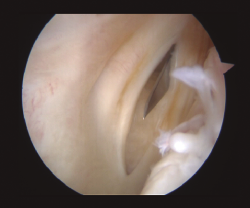

Este tipo de lesiones se pueden clasificar en 5 tipos(5)(Figura 1):

- Tipo 1: lesión de la rampa posterior.

- Tipo 2: lesiones parciales superiores.

- Tipo 3: lesiones parciales inferiores u ocultas.

- Tipo 4: lesiones completas.

- Tipo 5: lesiones dobles.

Figura 1. Visión a través del intercóndilo de lesión inferior oculta, que se detecta con la palpación a través del portal posteromedial.